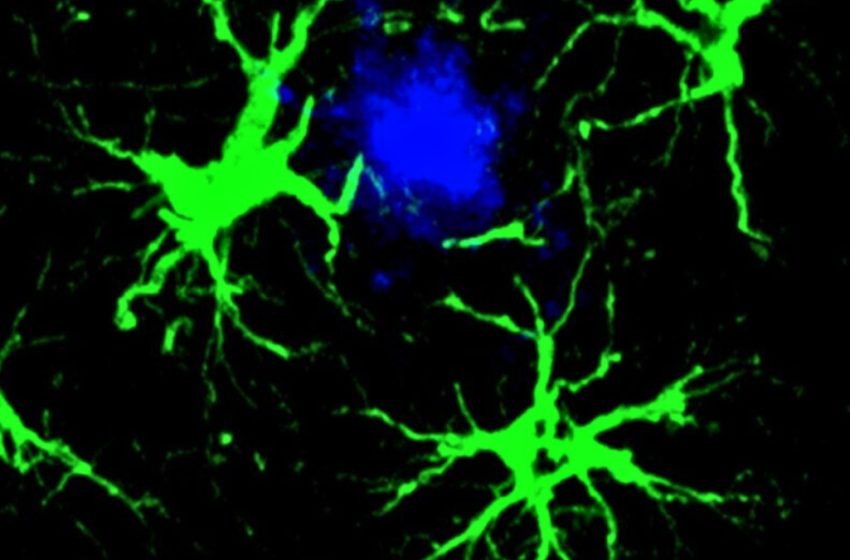

In the new study, researchers focused on star-shaped brain cells called astrocytes, which they engineered to hunt down the amyloid beta proteins associated with cognitive decline in Alzheimer’s.

“This study marks the first successful attempt at engineering astrocytes to specifically target and remove amyloid beta plaques in the brains of mice with Alzheimer’s disease,” says senior author Marco Colonna, pathologist at Washington University in the US.

Astrocytes normally perform a variety of important duties in the brain, including housekeeping, but this technique harnesses their collective power and leverages it against amyloid beta proteins.

Upon receiving this new assignment, astrocytes became singularly focused on clearing out amyloid beta plaques, a task at which they proved adept.